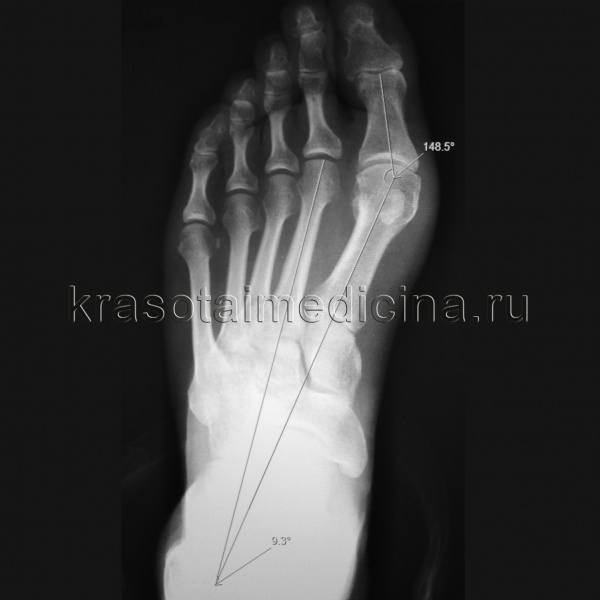

На следующем изображении показаны примеры высыпаний на коже после приема антибиотиков.